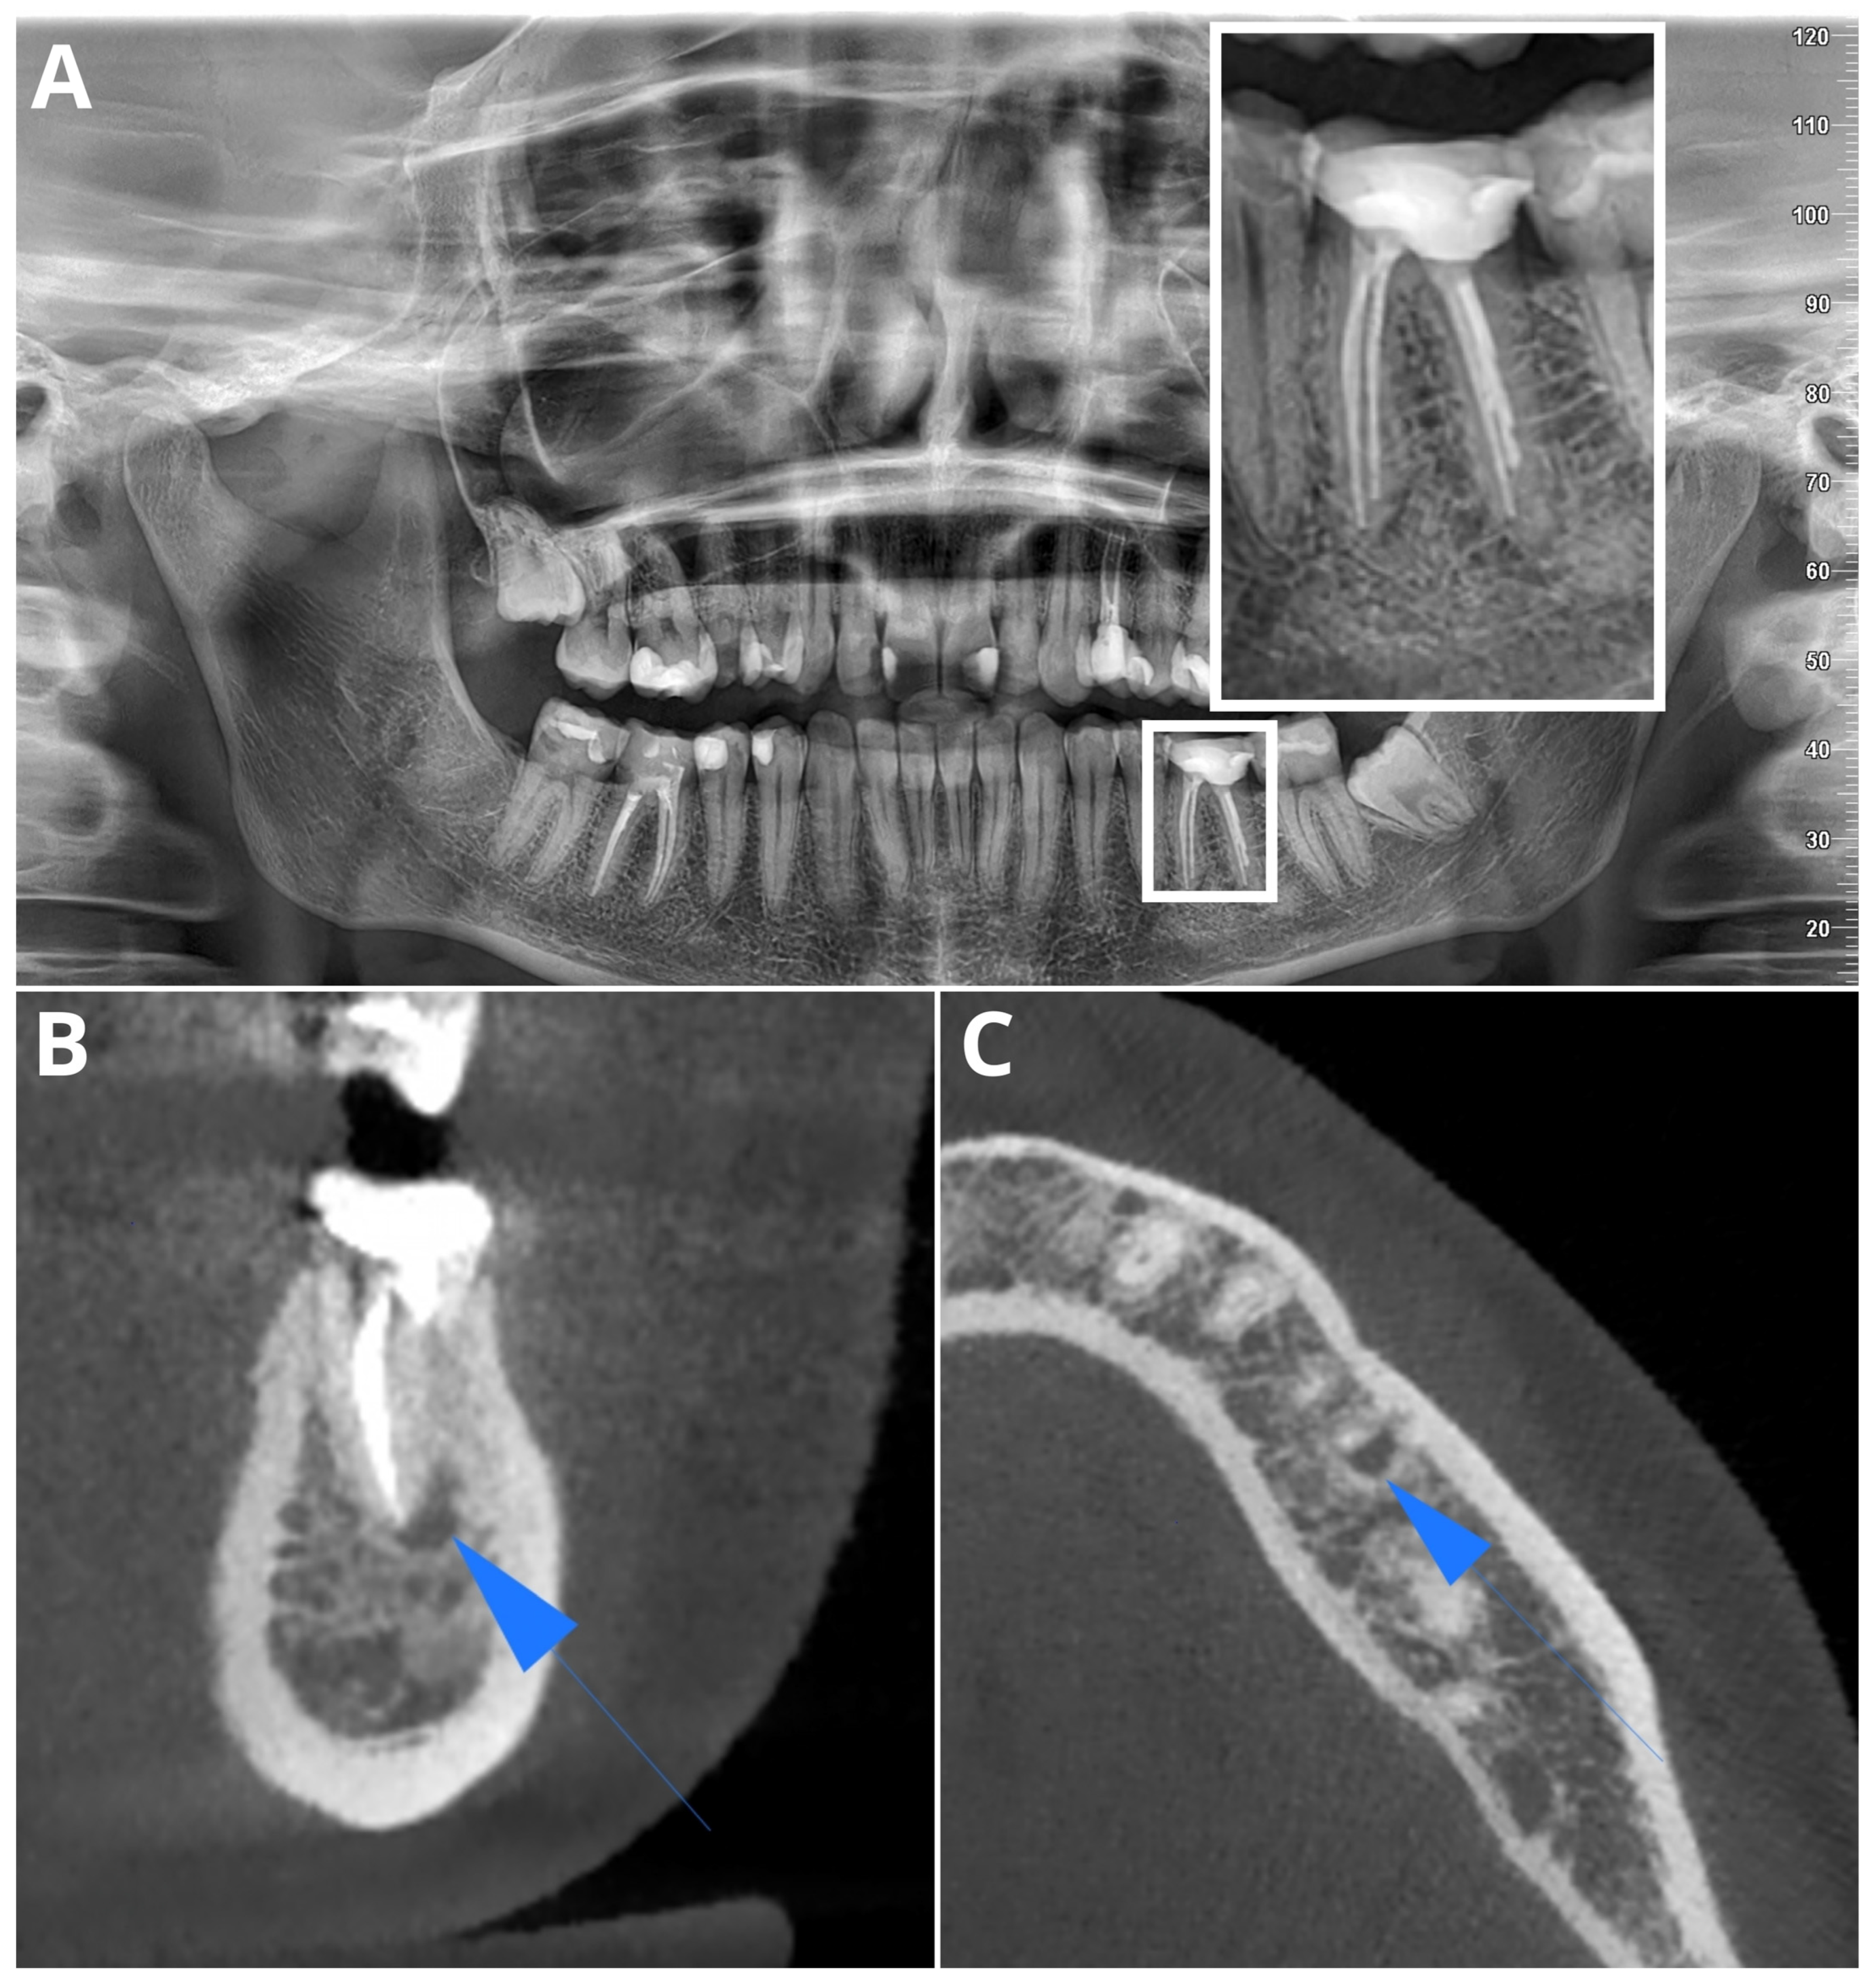

Periapical Lesions in Panoramic Radiography and CBCT Imaging—Assessment of AI’s Diagnostic Accuracy

2. Materials and Methods

2.1. Patients

2.2. Image Acquisition and Post-Processing